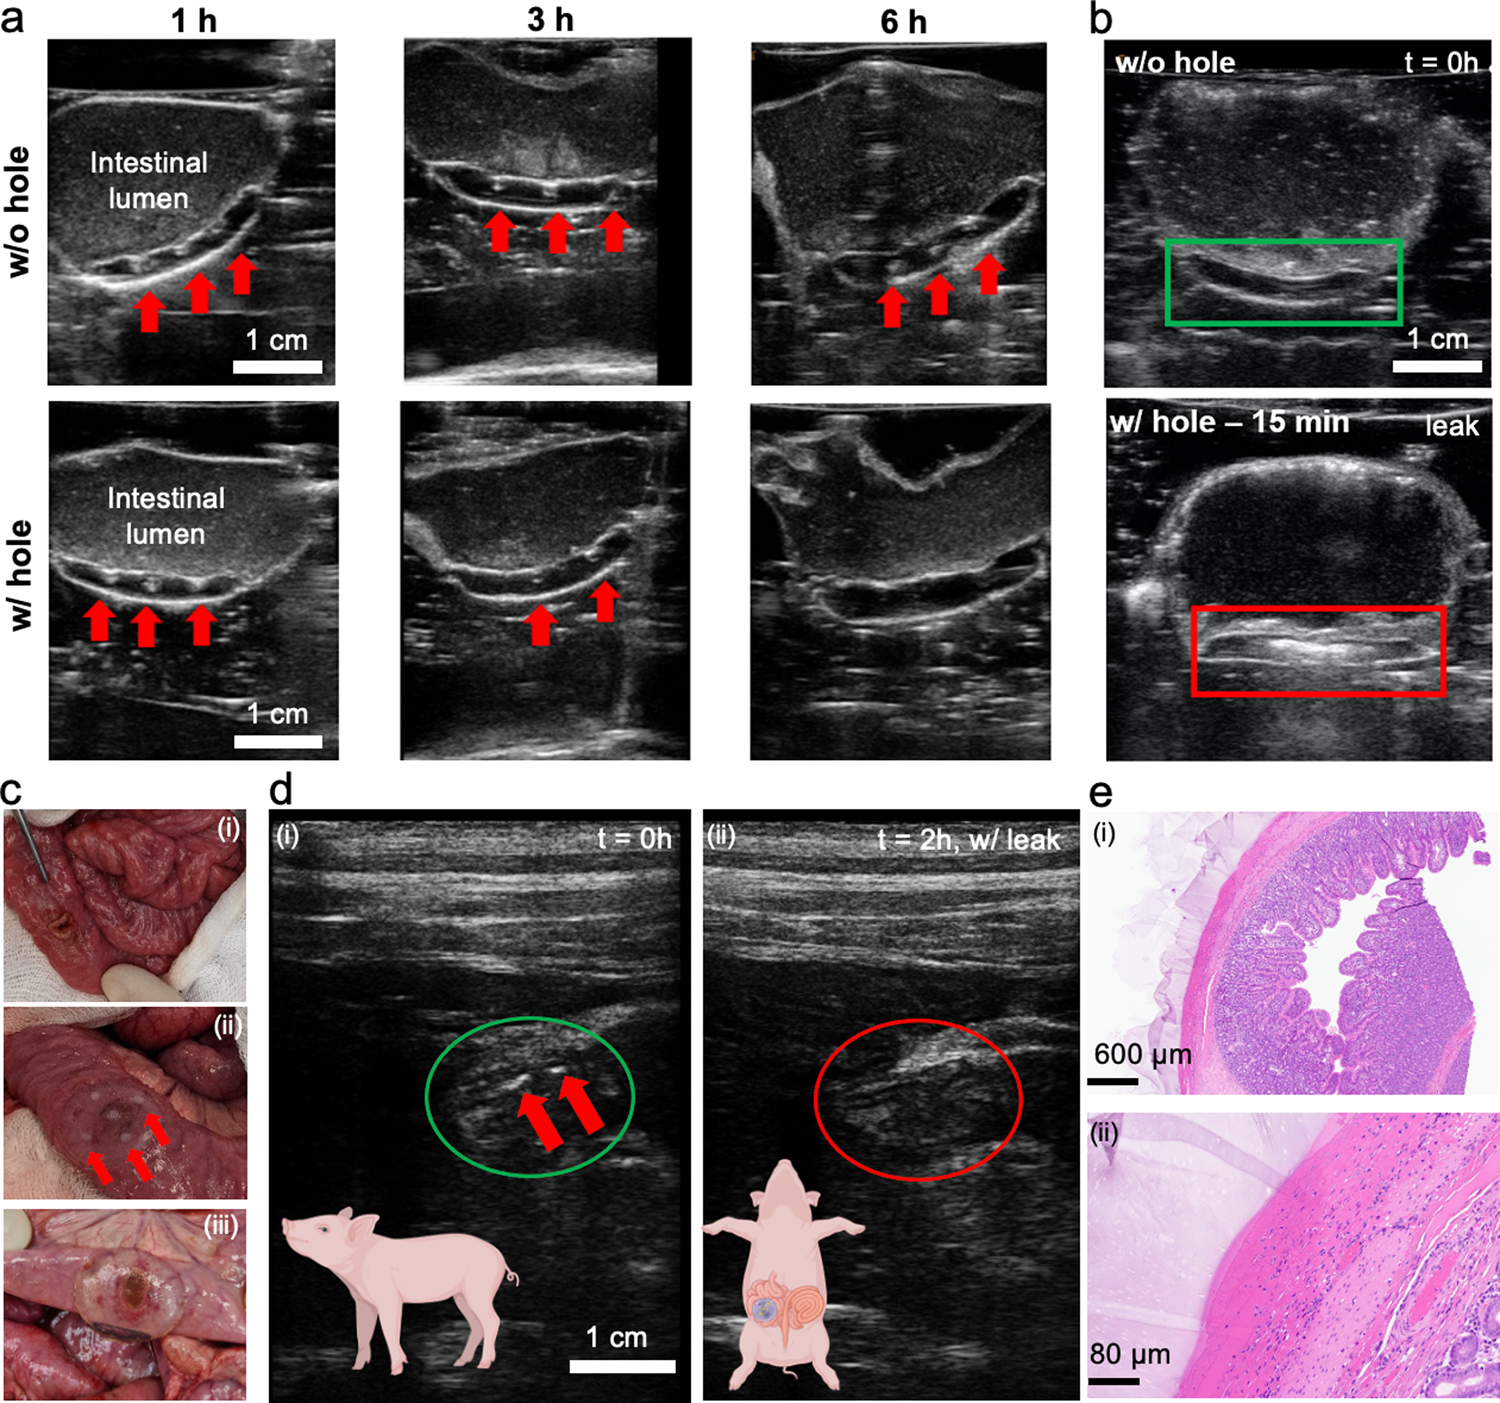

Fig. 5: Ultrasound-based leak detection ex vivo and in vivo.

Ex vivo ultrasound images obtained using an ipad controlled Clarius L7 HD probe of (a) a TurnOFF patterned hydrogel patch attached to intestine filled with SIF, equipped with a 4 mm hole simulating the perforation. The suture sites are monitored over six hours, showcasing pattern disappearance, N ≥ 3. b TurnON sensing element equipped hydrogel patch attached to an intestinal tissue model, filled with SGF indicating suture perforation by increased ultrasound scattering after fifteen minutes of contact with SGF, n ≥ 3. c In vivo application of TurnOFF DL-patches on piglet intestine with a defect. c-i 4 mm defect formation on live small porcine intestine. c-ii photograph of patch immediately after application on the defect. Sensing elements are clearly visible (red arrows). c-iii sealant patch 2 h post application on formed defect, presenting containment of digestive leak. d Ultrasound data recorded (d-i) immediately after patch application and surgical closure of the abdomen with a running suture. Sensing elements are discernible (red arrows). (ii), (d-ii) 2 h after application, sensing elements were not detectable anymore, in line with the disappearance of the opaque dots (c-iii). e Histological micrographs of intestinal tissue collected after euthanasia of the piglet shows firm attachment of the hydrogel to the serosa of the small intestine tissue and no visible tissue damage. Two samples were analysed yielding visually indistinguishable results. Figure wide color coding: red arrows—TurnOFF sensing element active. Figure 5d has been created using biorender.com.